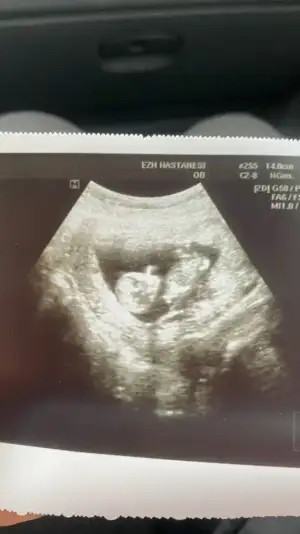

Papatyamaviss Papatyamaviss benim de mi belli olmaz.. ekledim en uygun foto bu 10.hafta bugüne ait

• 16800929872148500445775044353857.webp

16800929872148500445775044353857.webp

19,5 KB · Görüntüleme: 65